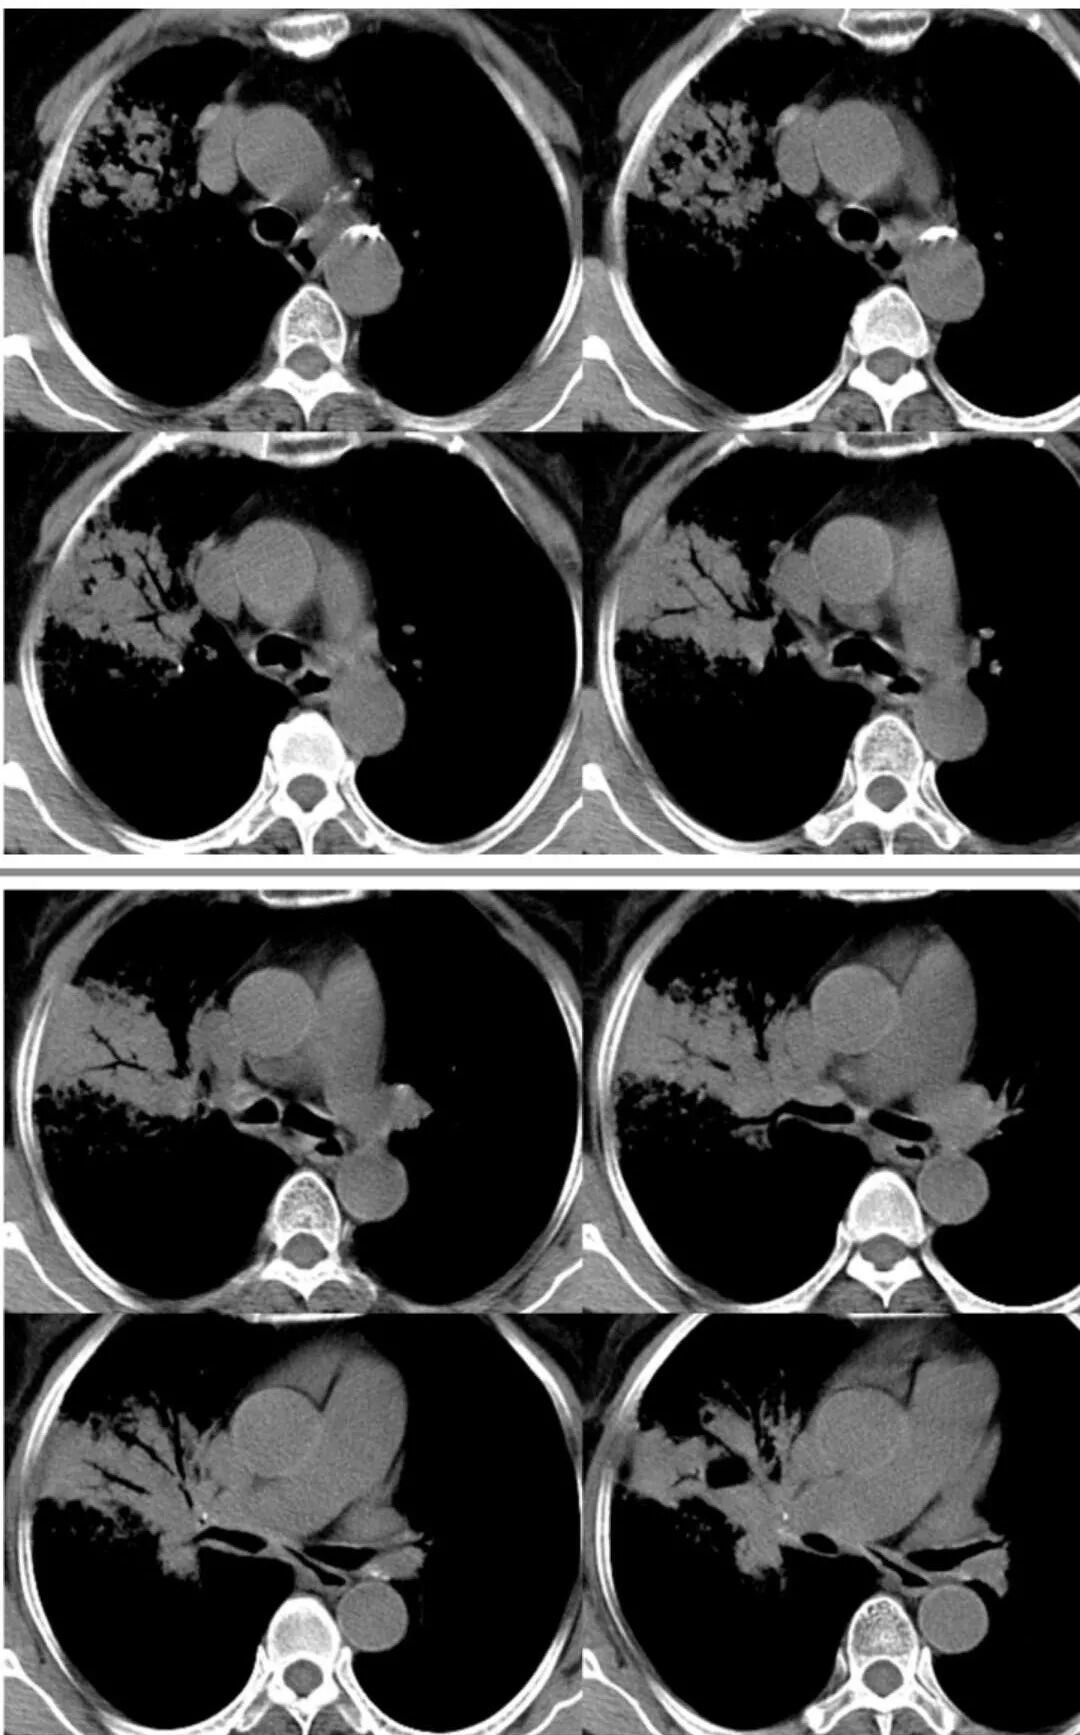

胸CT:右肺上叶实变内可见支气管充气征,近端支气管狭窄,远端扩张,周围可见毛玻璃影,右肺中叶支气管闭塞,并可见气道壁钙化,右肺中叶体积缩小,实变内可见空洞,并可见气液平面,空洞周围可见毛玻璃样影,右肺下叶支气管开口狭窄,右肺门淋巴结肿大。纵隔窗可见病灶与壁层胸膜间隙增宽,考虑良性病变-----感染性病变------TB?

右肺上叶病变,内见钙化及空洞,支气管可见,考虑结核伴出血。

右中叶支气管完全阻塞伴厚壁空洞,右上叶支气管不全阻塞伴大片GGN,右下部分GGN考虑腺鳞癌,结核待排。

老年女性,慢性病程,咳嗽伴白色粘液痰,无发热腹痛,糖尿病,白细胞及C反应蛋白不高,血沉快,铁蛋白高。胸部CT,右肺上叶大片状实变伴磨玻璃密度影,边界不清,边缘局部膨隆,叶裂弧形下坠,实变影宽基底与胸膜相贴;右肺下叶前基底段见类似病灶;右肺中叶不张并空洞形成,空洞内见气液平面;综合考虑右肺上叶及下叶肺炎型肺癌,右肺中叶结核。

这里是中叶的不张和空洞,有钙化,结核确实也不能排除

主病灶应该是粘腺腺癌,右中叶不张?,内空洞,壁光滑,考虑感染

1.王老师的病理说明粘液腺癌的破坏力弱,对血管和支气管破坏少,所以理论上空洞少,这个空洞很明确。

2.南大理论:粘液腺癌起源于外周,所以主体病灶位于胸膜下多见,这个病人主体病灶位于中心,外周磨玻璃为主,部分磨玻璃模糊

3.熊老师告诉我们:肺结核可以有磨玻璃,这个我以前一直不知道,右肺门淋巴结有钙化,病灶内纵膈窗隐约细细点状钙化,所以结核磨玻璃可以,

这些层面的支气管我觉得像结核的狭窄后扩张,

中叶的体积缩小,也不是粘液腺癌能完全解释,